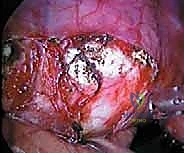

إصلاح تمزق الكفة المدورة المفتوح في الكتف: دليل شامل للمرضى مع الأستاذ الدكتور محمد هطيف في صنعاء

تعرف على جراحة إصلاح تمزق الكفة المدورة المفتوح، تجميل الأخرم، واستئصال الترقوة البعيدة. دليل شامل للأعراض والتشخيص والعلاج مع الأستاذ الدك…